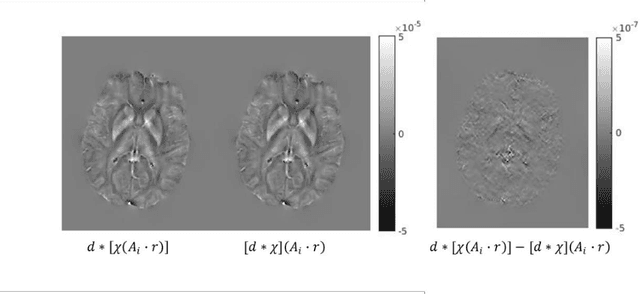

Abstract:Purpose: To improve the generalization ability of convolutional neural network (CNN) based prediction of quantitative susceptibility mapping (QSM) from high-pass filtered phase (HPFP) image. Methods: The proposed network addresses two common generalization issues that arise when using a pre-trained network to predict QSM from HPFP: a) data with unseen voxel sizes, and b) data with unknown high-pass filter parameters. A network fine-tuning step based on a high-pass filtering dipole convolution forward model is proposed to reduce the generalization error of the pre-trained network. A progressive Unet architecture is proposed to improve prediction accuracy without increasing fine-tuning computational cost. Results: In retrospective studies using RMSE, PSNR, SSIM and HFEN as quality metrics, the performance of both Unet and progressive Unet was improved after physics-based fine-tuning at all voxel sizes and most high-pass filtering cutoff frequencies tested in the experiment. Progressive Unet slightly outperformed Unet both before and after fine-tuning. In a prospective study, image sharpness was improved after physics-based fine-tuning for both Unet and progressive Unet. Compared to Unet, progressive Unet had better agreement of regional susceptibility values with reference QSM. Conclusion: The proposed method shows improved robustness compared to the pre-trained network without fine-tuning when the test dataset deviates from training. Our code is available at https://github.com/Jinwei1209/SWI_to_QSM/